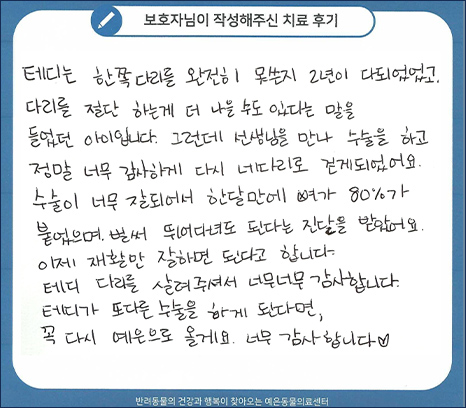

치료 후기

테디는 한쪽 다리를 완전히 못쓴지 2년이 다되었고, 다리를 절단 하는게 더 나을 수도 있다는 말을

들었던 아이입니다. 그런데 선생님을 만나 수술을 하고 정말 너무 감사하게 다시 네다리로 걷게되었어요.

수술이 너무 잘되어서 한달만에 뼈가 80%가 붙었으며, 벌써 뛰어다녀도 된다는 진단을 받았어요.

이제 재활만 잘하면 된다고 합니다. 테디 다리를 살려주셔서 너무너무 감사합니다.

테디가 또 다른 수술을 하게 된다면, 꼭 다시 예은으로 올게요. 너무 감사합니다.

테디 수술 전

테디 수술 3주 후